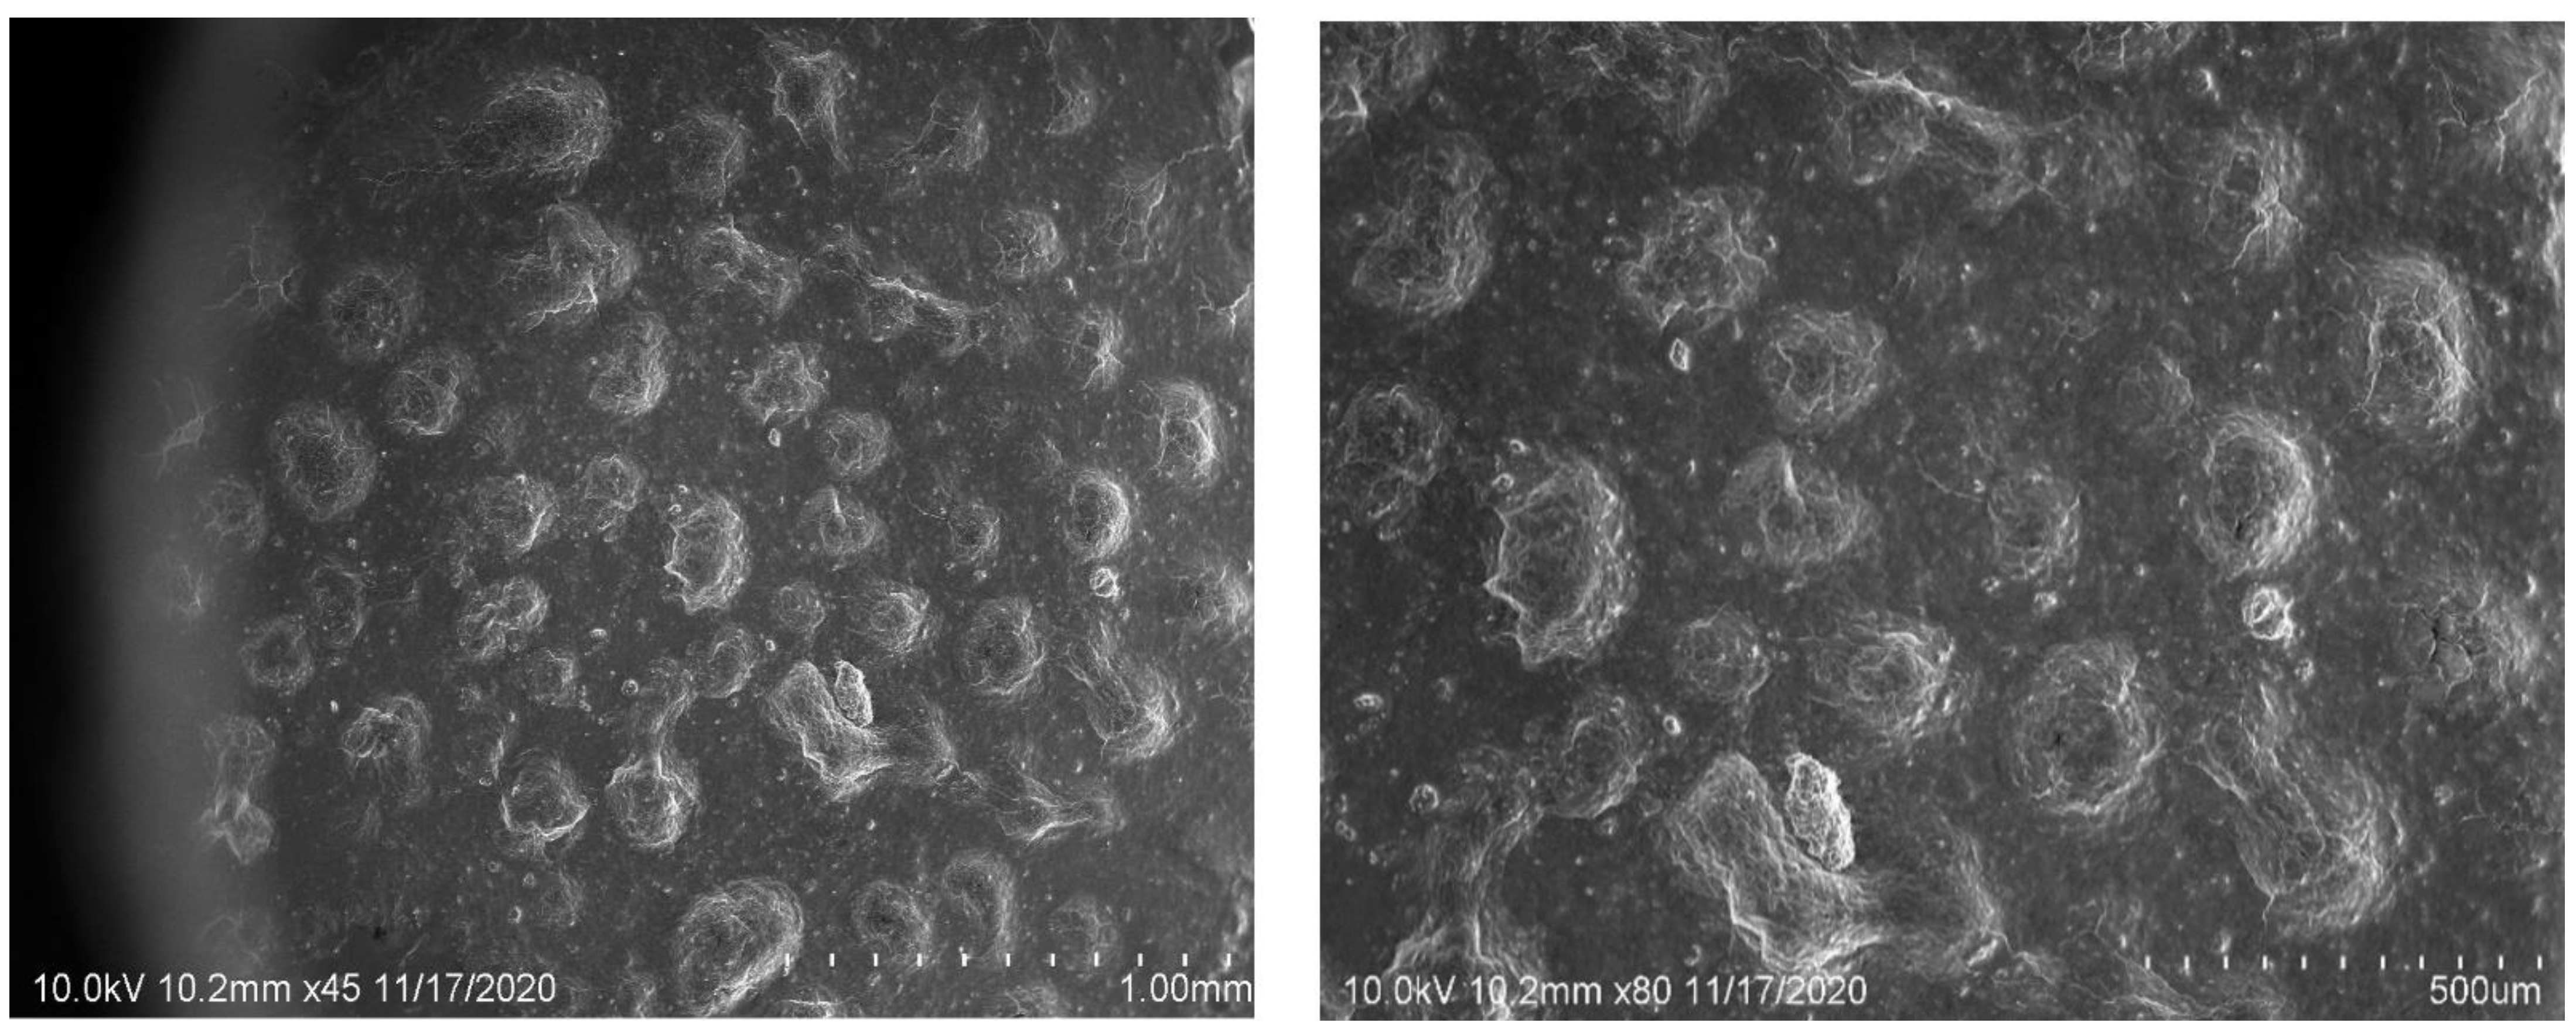

2.6. SEM Image Studies

4.9.4. SEM